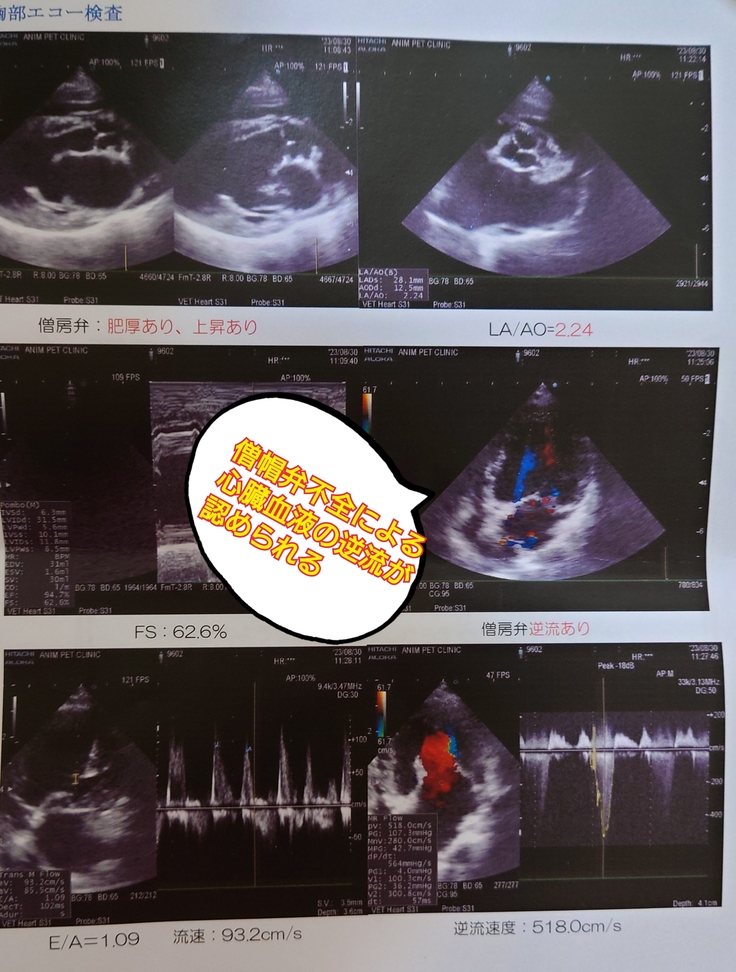

2.心臓の僧帽弁閉鎖不全の状態

心臓のエコー検査の結果です。

心臓の僧帽弁は反り返っている状態で血液が逆流し、

右心室へ圧力がかかって、肺に水がたまる状態は常態化しています。

ただ重症の子に比べるとその圧力は急激ではなく、

緩やかなもの、とのことです。